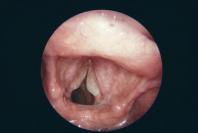

La laryngoscopie flexible directe ou indirecte est recommandée en cas de symptômes persistants > 3 semaines; les signes en cas de laryngite sont un érythème de la muqueuse de léger à marqué, laquelle peut aussi être œdémateuse. En cas de reflux, on observe un gonflement de la paroi interne du larynx et une rougeur des aryténoïdes.